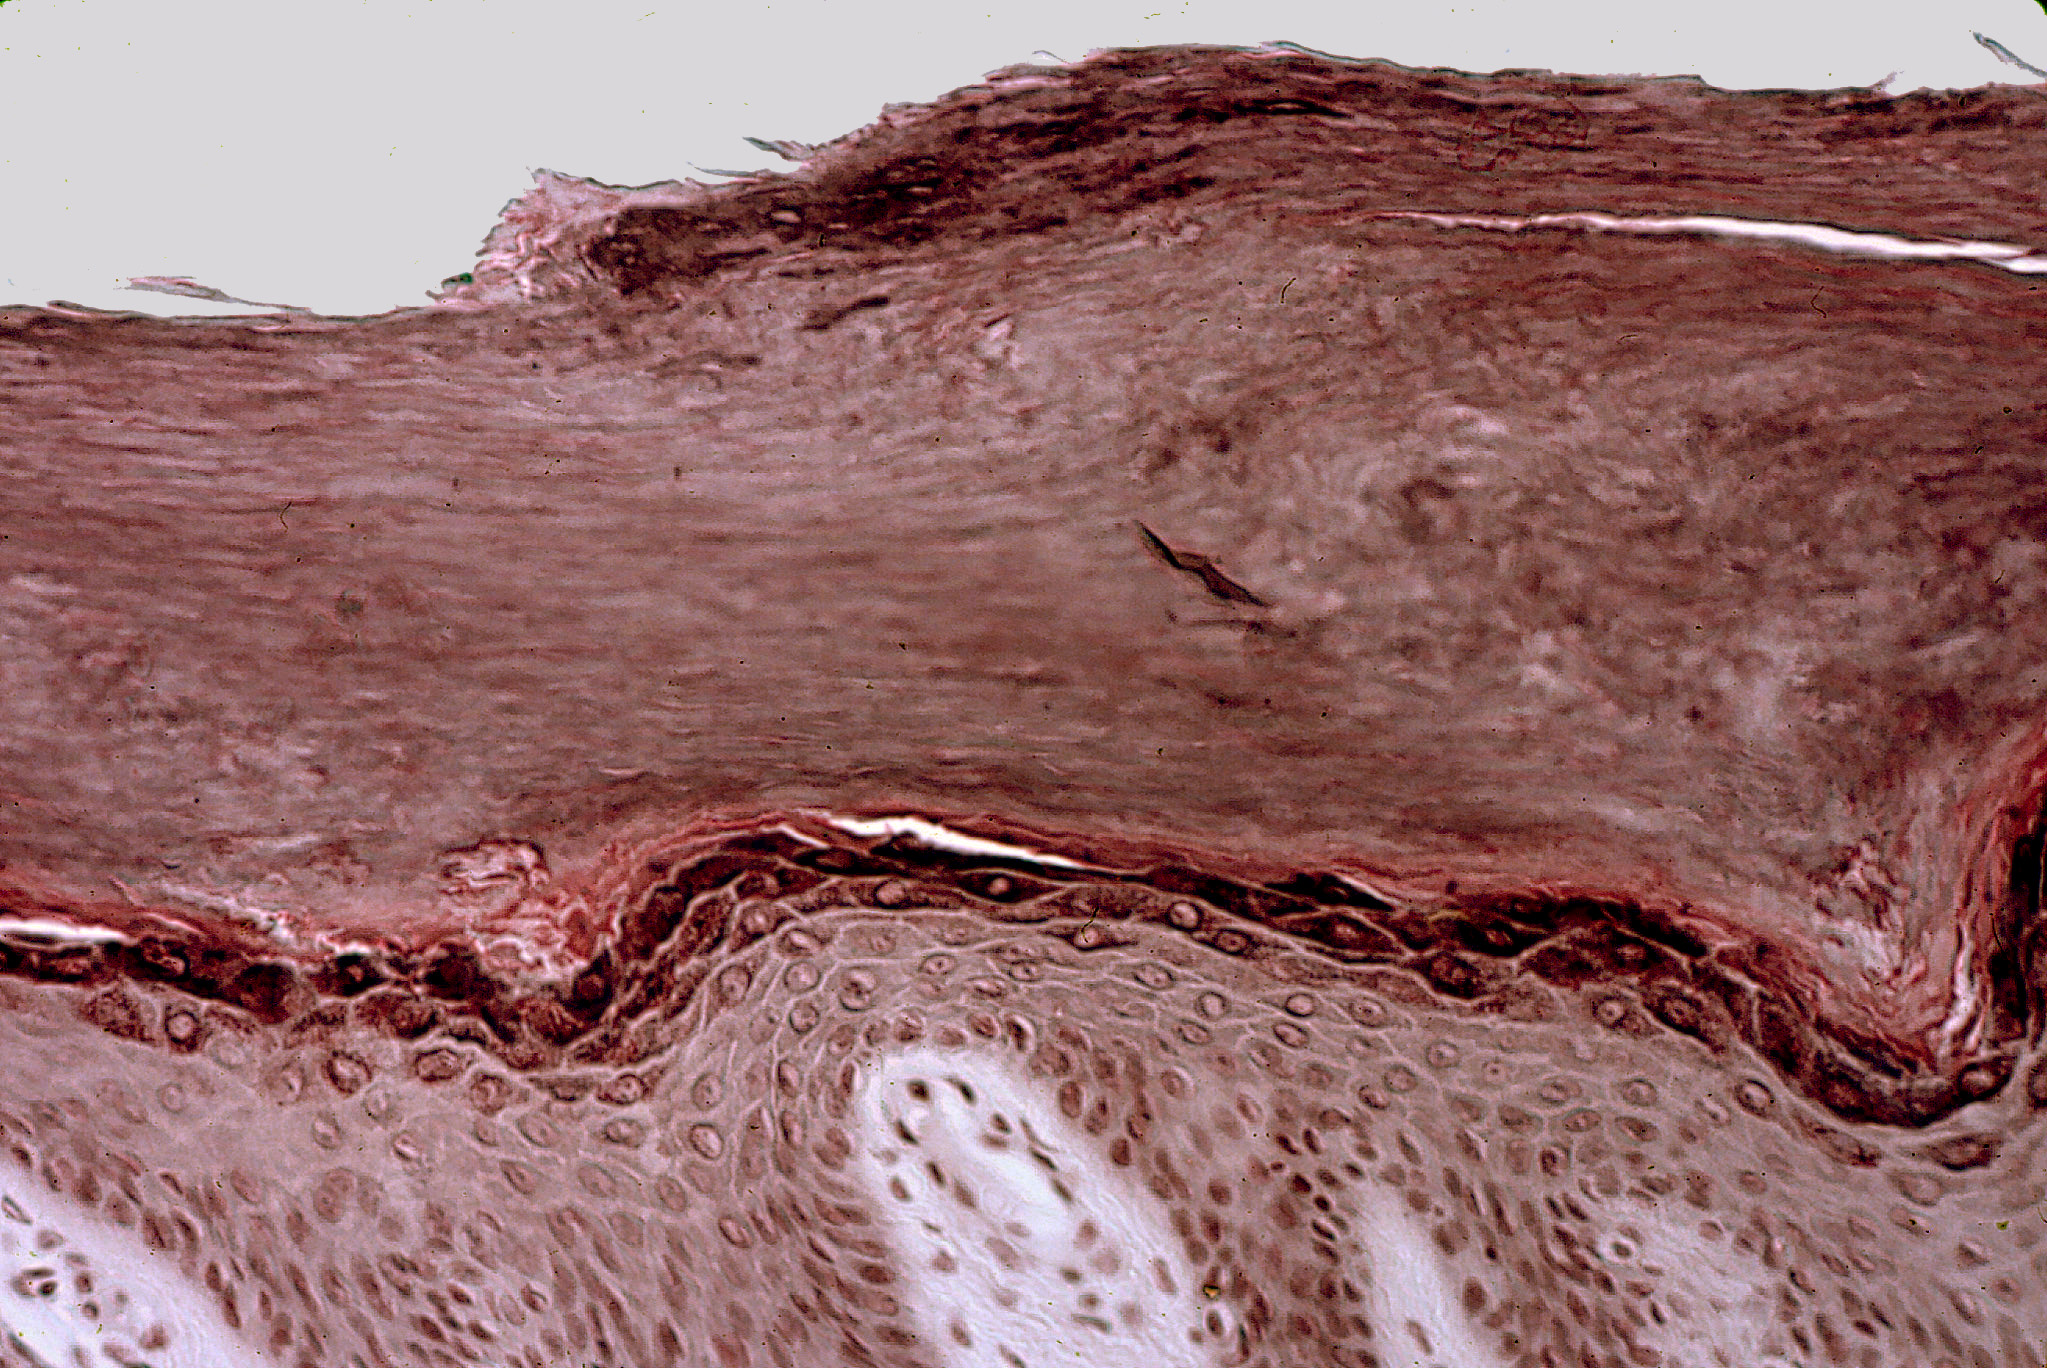

Corte de piel